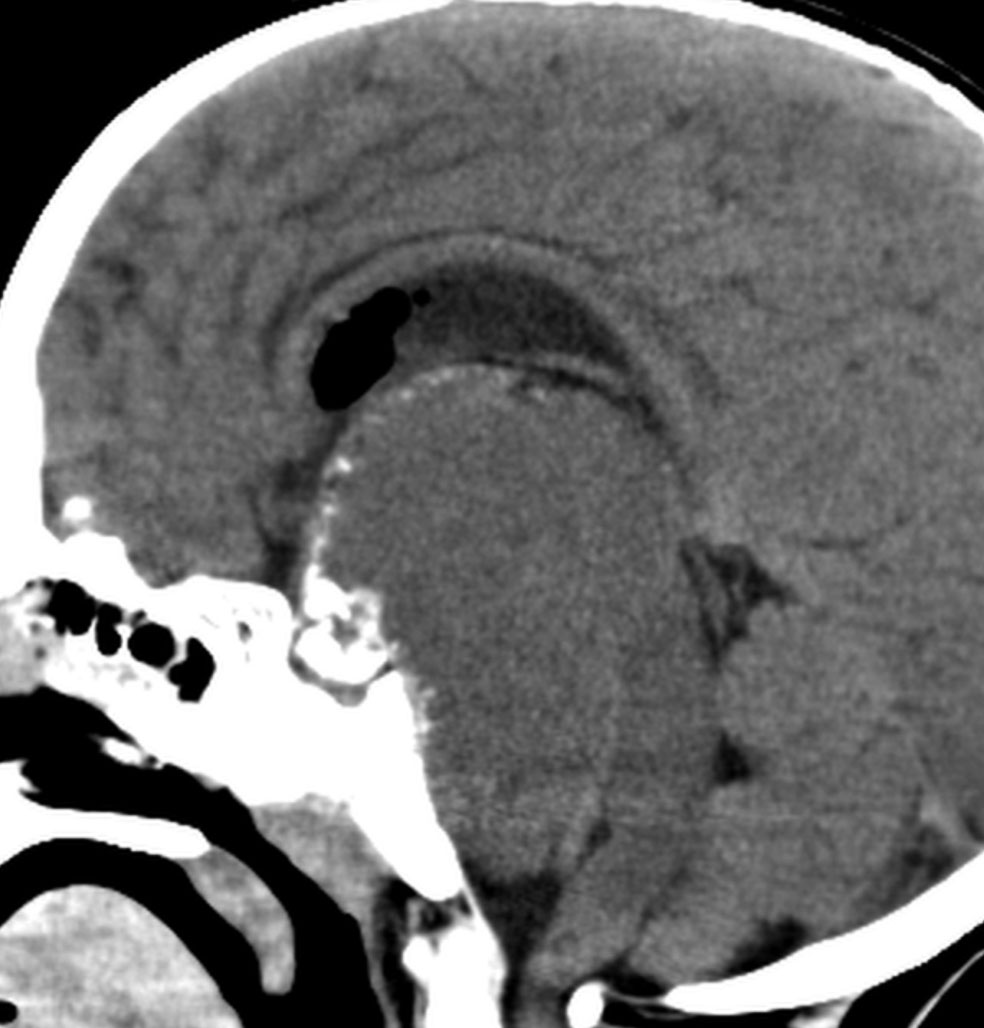

この子の症状は頭痛だけ。両親はなぜ気づかなかったのかと疑問を持ちますが,巨大になるまで症状が出ないこともあるのです。左のCTで腫瘍の周囲にバラバラと白い点状の石灰化があるので診断できます。左の視床下部から発生したクラニオでした。開頭手術しますが超高難易度です,怖いです (┯_┯) 複数回開頭手術になりましたが結果的に全摘出できています (by Dr 山本哲哉)。

危険な のう胞性 頭蓋咽頭腫 cystic craniopharyngioma

上に示した例は,巨大な「のう胞性」頭蓋咽頭腫でもあります。袋の中に液体が入っているのを「嚢胞 cyst」といいます。大部分は液体なので,袋を破れば腫瘍は簡単に小さくなります。